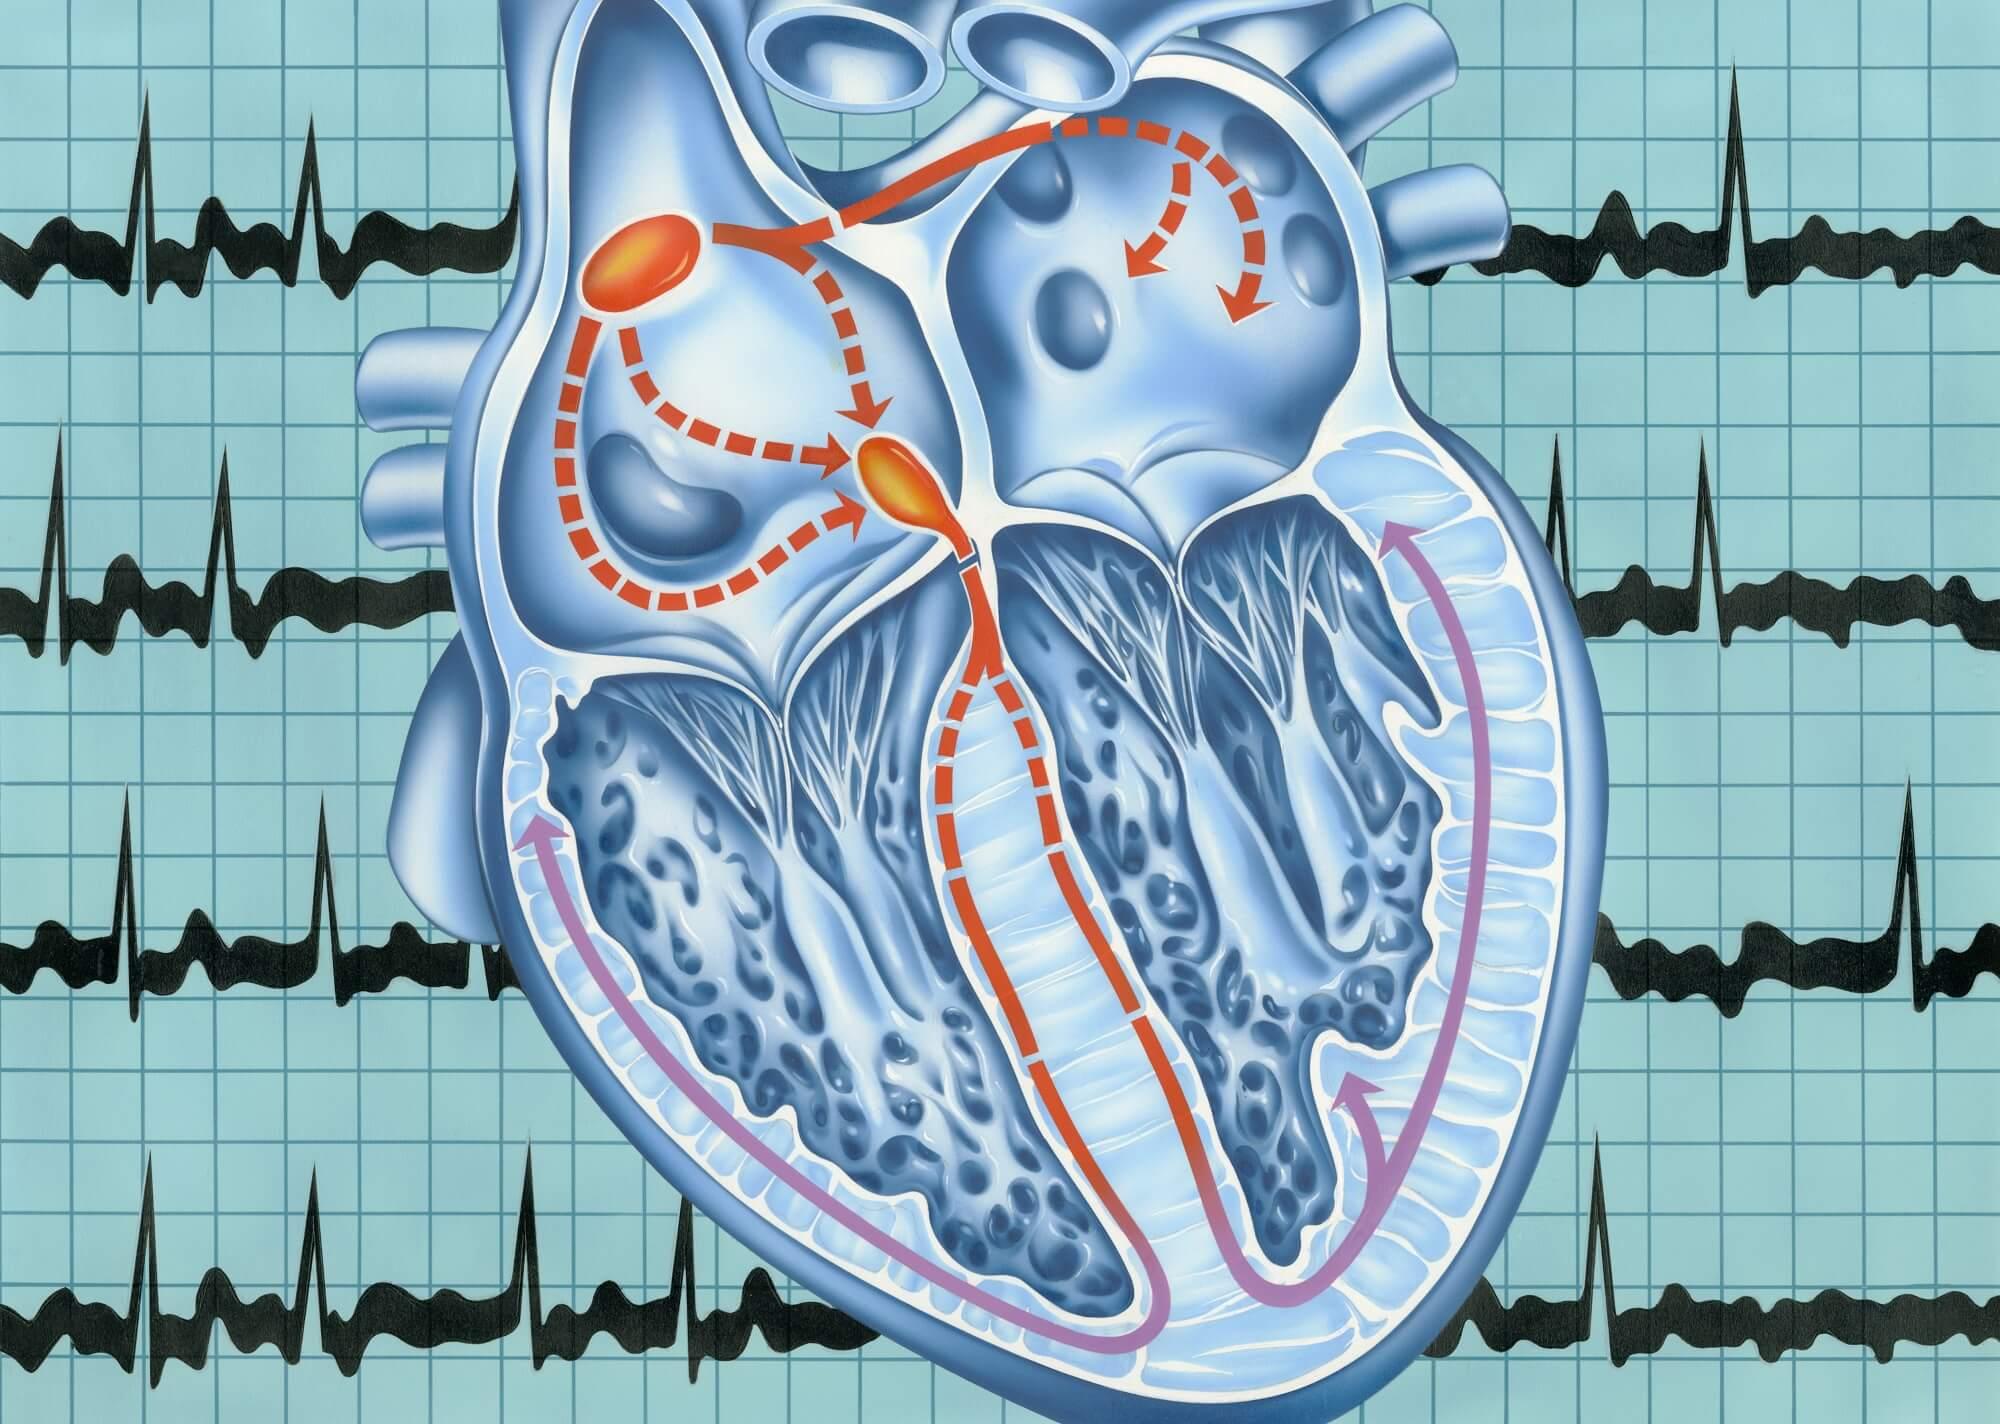

The atrial fibrillation market is undergoing significant transformation driven by rising prevalence of cardiovascular diseases, aging populations, and advancements in medical technology. With Afib being the most common sustained arrhythmia worldwide, healthcare systems are increasingly focused on prevention, diagnosis, and treatment solutions to manage this condition effectively. The market...